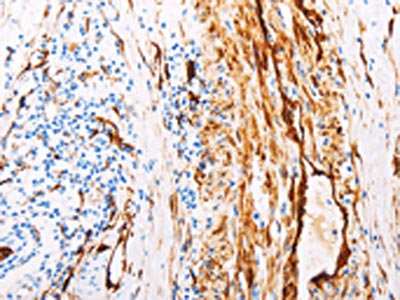

The image on the left is immunohistochemistry of paraffin-embedded Human colon cancer tissue using CSB-PA546098(TGM2 Antibody) at dilution 1/15, on the right is treated with fusion protein. (Original magnification: ×200)